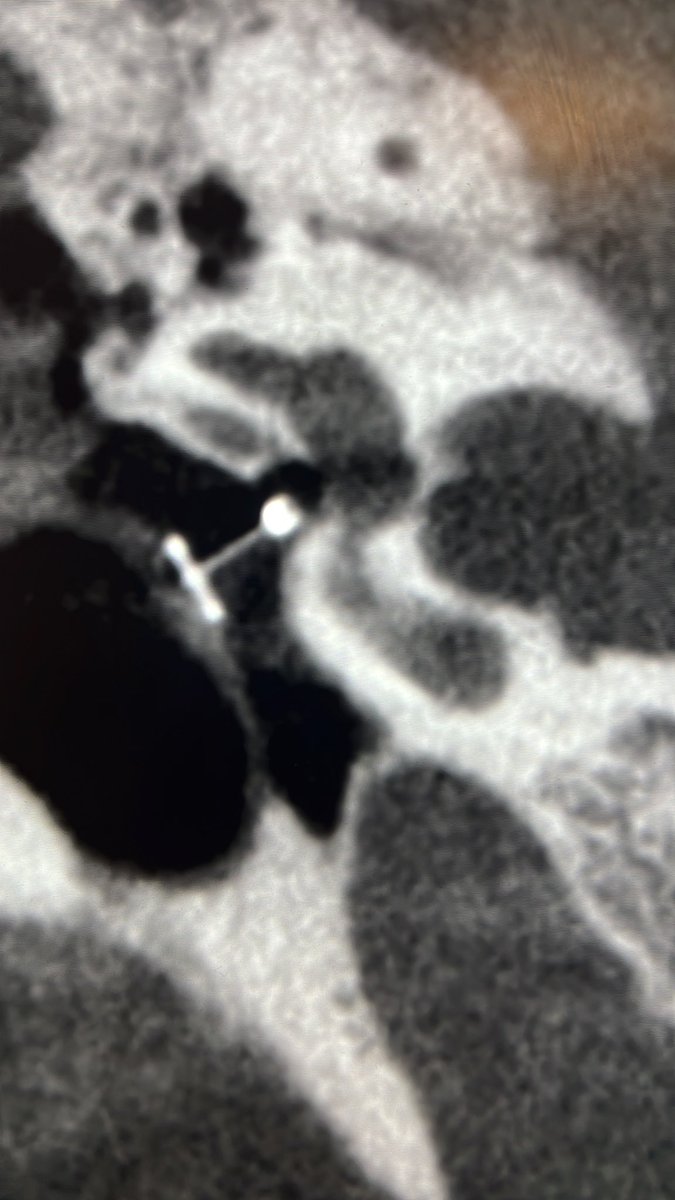

Tip of the day 💡: The pituitary and it’s stalk can enlarge and enhance like this during puberty. Physiology is a range of normality.